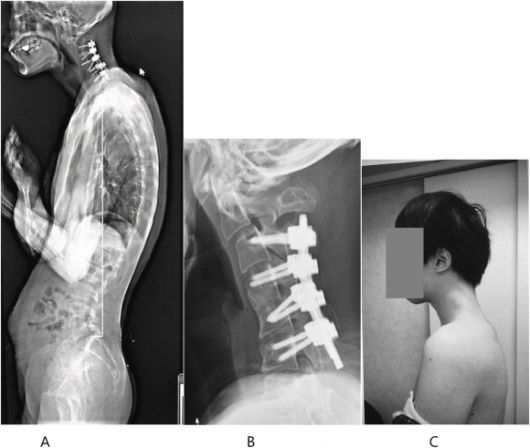

이에 의료진은 수술을 택했다. 먼저 척추뼈의 튀어나온 부분과 경막에 생긴 흉터 같은 조직 일부를 제거했다.

이후 목뼈에 나사와 금속 막대를 삽입해 자세를 교정했다.

수술 후 6개월 만에 환자는 머리를 수평으로 쉽게 유지할 수 있게 됐다. 그 결과 음식을 삼키는 어려움도 없어져 식사를 정상적으로 할 수 있게 됐고, 전반적인 자세와 삶의 질이 크게 개선됐다.

수술 후 호전된 척추와 목뼈 상태. 일본정형외과 학회지(JOS)의 사례 연구집 논문 캡처 |

퇴원 후 스마트폰 게임을 하는 습관은 다시 이어졌으나 1년 뒤 추적 관찰한 결과 전과 같은 심각한 목 꺾임은 재발하지 않았다.